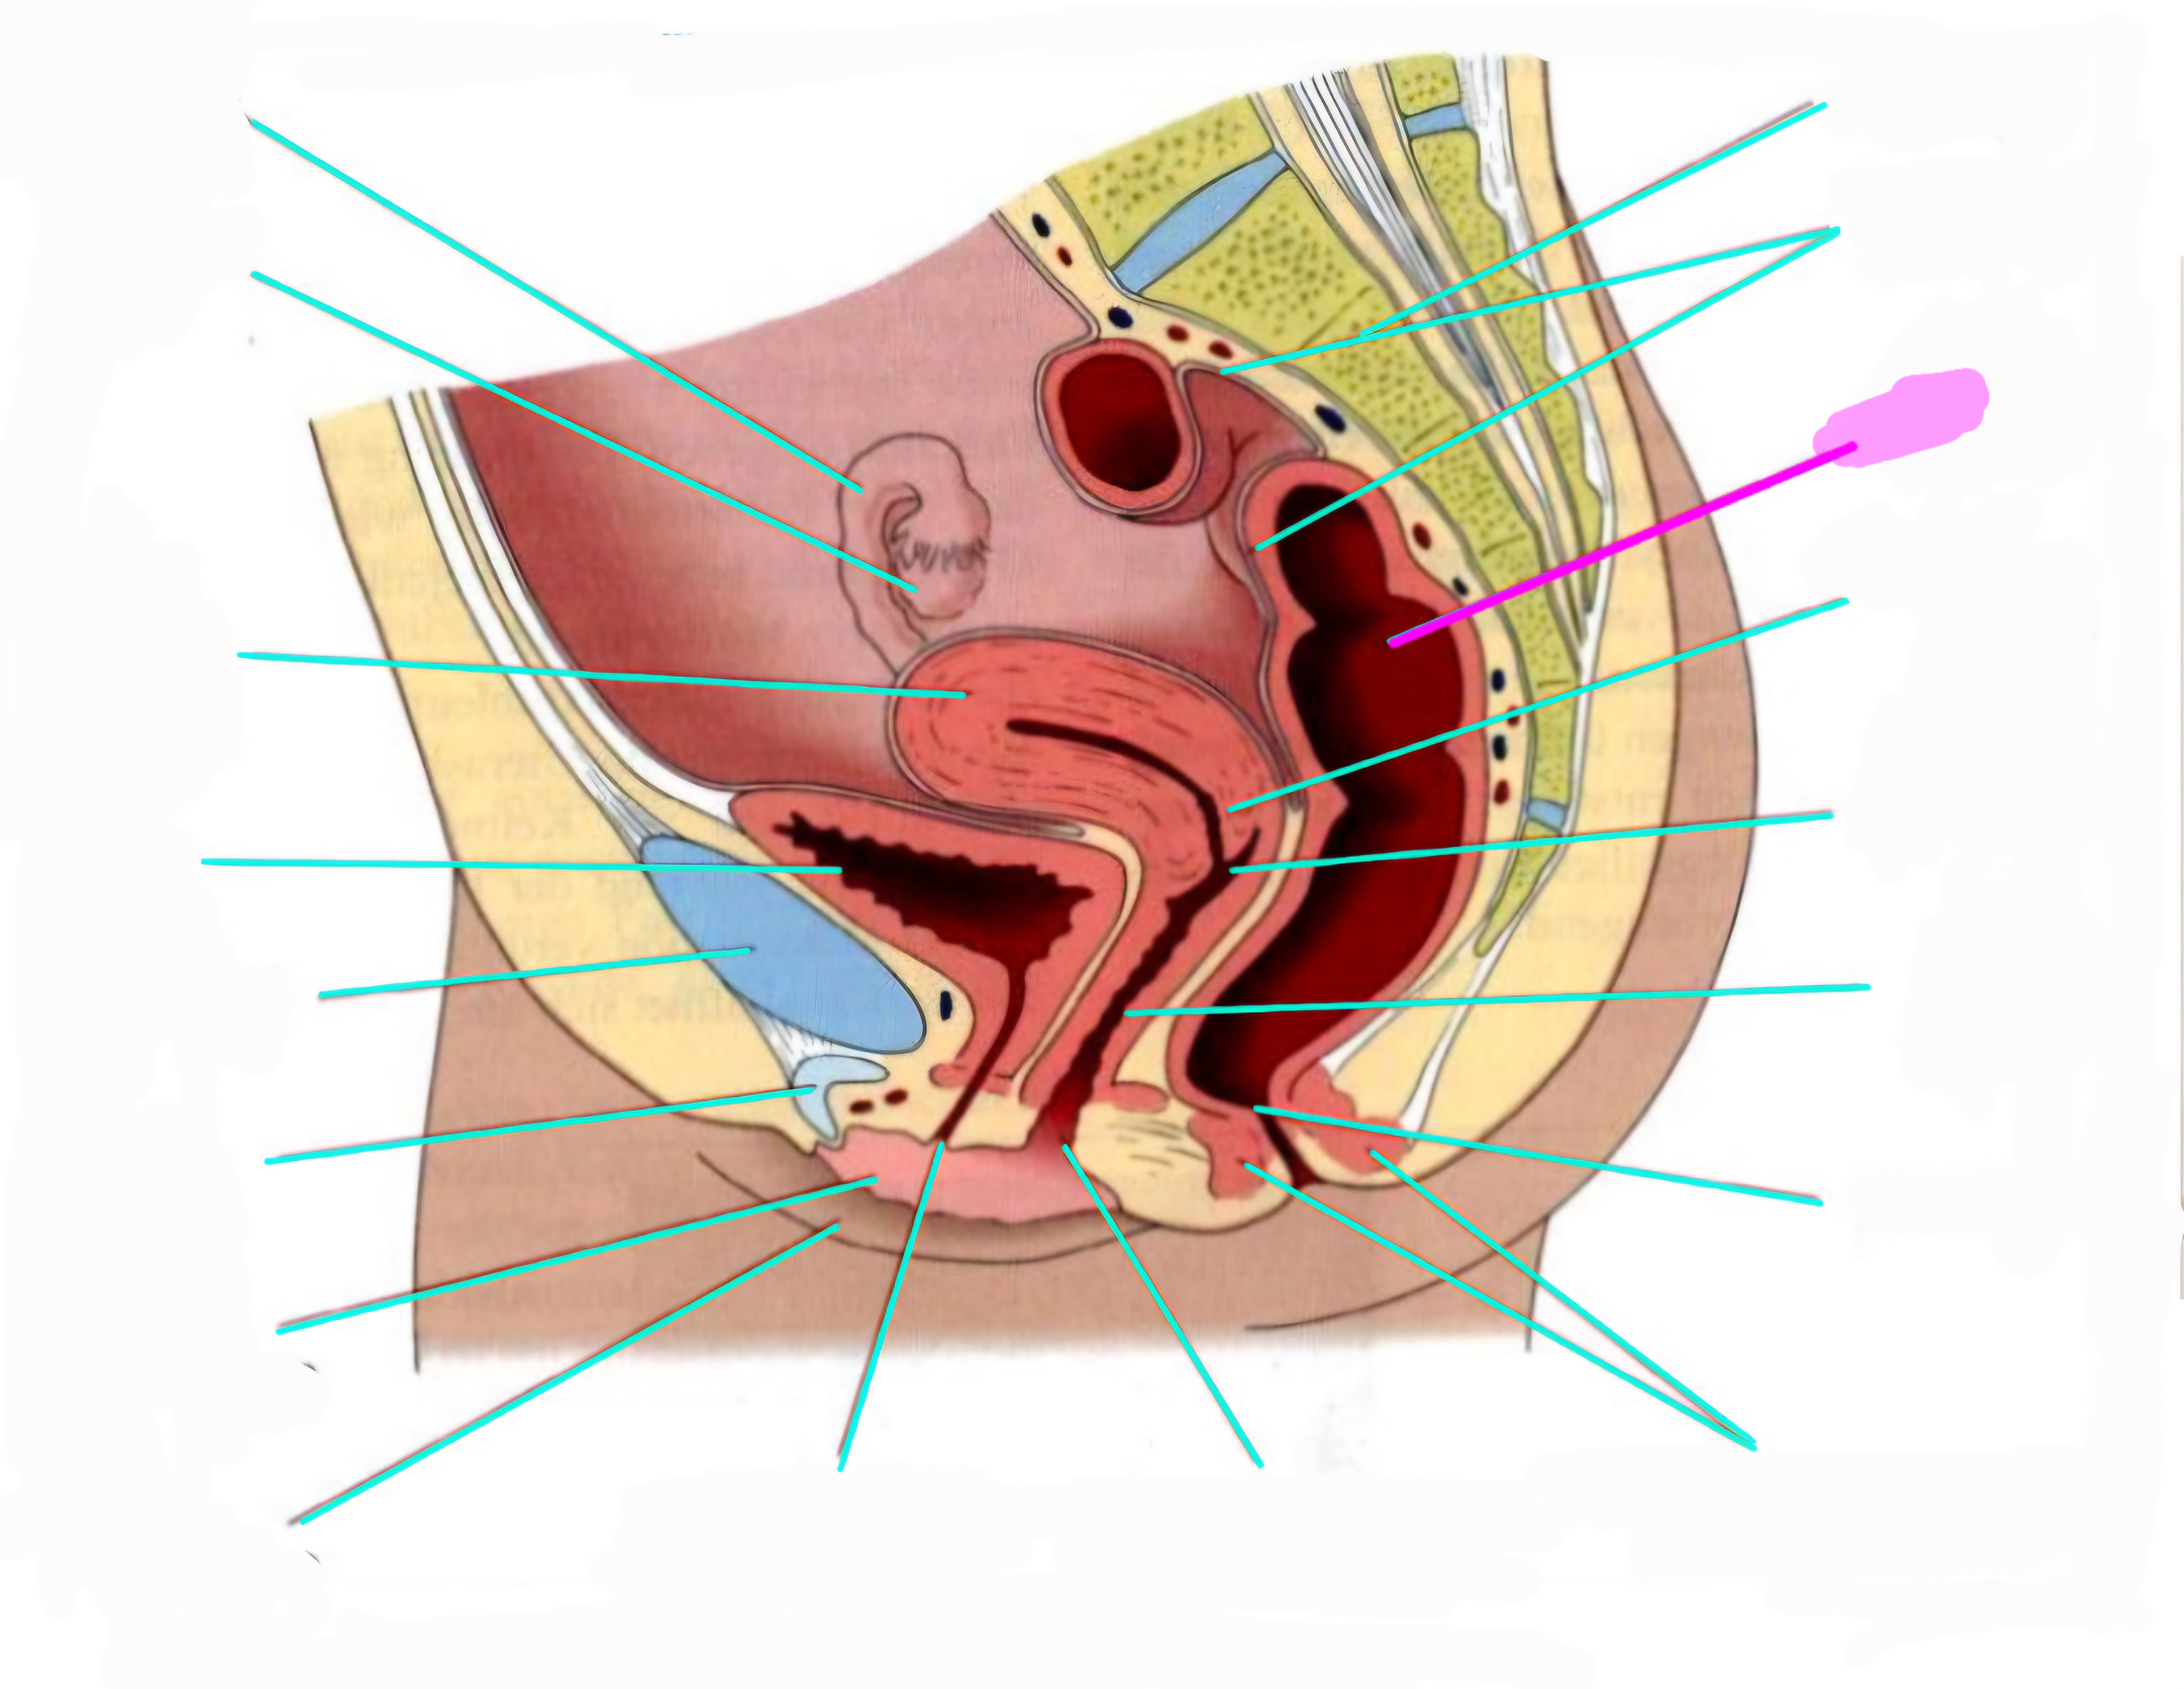

wbl. genital Anatomie

19 Terms

Tubea uterina (Eileiter)

Ovar (Eierstock)

Uterus (Gebärmutter)

Vesica Urinaria (Harnblase)

Symphyse

Klitoris

Labia minor pudendi (kleine schamlippen)

Labia Majoran pudendi (große Schamlippe)

Urethra (Harnröhre)

Introitus vaginae (Scheideneingang)

Sphincter ani externes (äußere Afterschließmuskel)

Anus (After)

Vagina (Scheide)

Portio (äußerer Muttermund)

Rektum (Mastdarm)

Zervix (Gebärmutterhals)

Peritoneum (Bauchfell)

Os sacrum (Kreuzbein)

Uterus: Topographie und Aufbau - wie groß ist er und wo liegt er?

7-8cm lang, Form einer umgedrehten Birne

Lage: im kleinen Becken zwischen Blase und Rektum

Antiversio: nach vorne geneigt, steht im Winkel zur Scheide

Antiflexio: in sich selbst geknickt, nach vorne abgebogen öber die Blase